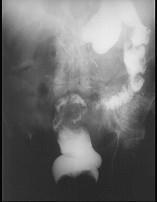

问题 女,50岁,便血10余年,加重1年(连续出血),近2个月大便时肛门常滴鲜血,量较多,X线检查如图,最可能的诊断是 ( )

选项 A.直肠癌 B.直肠绒毛状腺瘤 C.直肠淋巴瘤 D.直肠转移瘤 E.直肠结核

答案 B